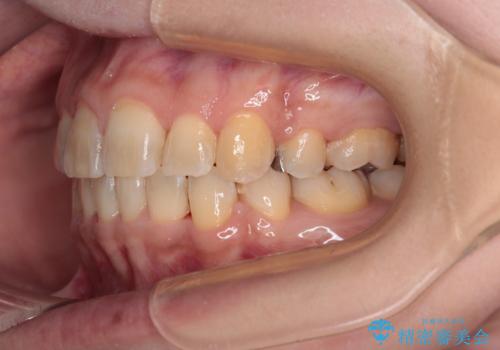

後戻りにリカバリーに少し時間を要しましたが、1年強の期間で無事に治療を終えることができました。